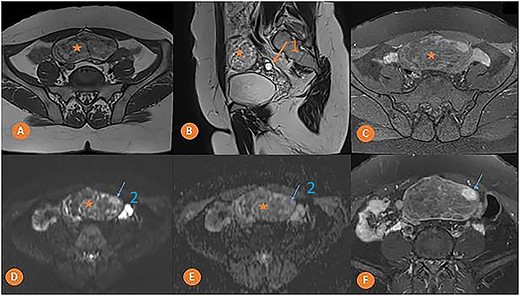

MRI was done to determine the precise characteristics of this mass. It showed a round, suprauterine mass near the left ovary, with a thin wall, containing a fatty component (T1 and T2 hyperintense, and T1 FS) with a T2 hyperintense, T1 hypointense solid component, with a high signal in diffusion-weighted imaging (DWI) and strong enhancement. MRI findings pointed to the presence of a left ovarian dermoid cyst with a potentially-malignant fleshy component classified as O-RADS MRI 5 (Fig. 2).

Pelvic MRI in axial T1 (A), sagittal T2 (B), axial T1 FS (C), axial DWI (D) with ADC mapping (E), and axial T1 injected (F) slices showing a median pelvic mass (star) lateralized on the left in contact with the homolateral ovary (arrow 1) with heterogeneous signal, mostly hyper intense in T1 and T2. It fades after removal of the fat and is not diffusion-restrictive except for a small nodular area on the left anterolateral side (arrow 2) which takes on strong contrast after injection of the gadolinium chelate.